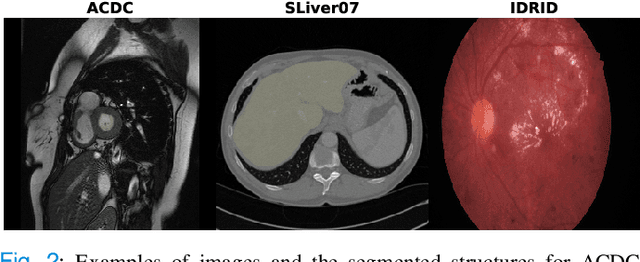

Abstract:Generative Adversarial Networks (GANs) have become increasingly powerful, generating mind-blowing photorealistic images that mimic the content of datasets they were trained to replicate. One recurrent theme in medical imaging is whether GANs can also be effective at generating workable medical data as they are for generating realistic RGB images. In this paper, we perform a multi-GAN and multi-application study to gauge the benefits of GANs in medical imaging. We tested various GAN architectures from basic DCGAN to more sophisticated style-based GANs on three medical imaging modalities and organs namely : cardiac cine-MRI, liver CT and RGB retina images. GANs were trained on well-known and widely utilized datasets from which their FID score were computed to measure the visual acuity of their generated images. We further tested their usefulness by measuring the segmentation accuracy of a U-Net trained on these generated images. Results reveal that GANs are far from being equal as some are ill-suited for medical imaging applications while others are much better off. The top-performing GANs are capable of generating realistic-looking medical images by FID standards that can fool trained experts in a visual Turing test and comply to some metrics. However, segmentation results suggests that no GAN is capable of reproducing the full richness of a medical datasets.